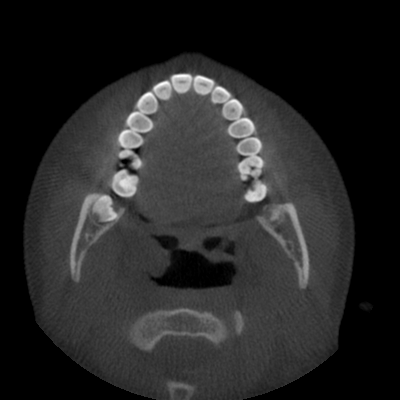

As a useful technology for radiographic imaging, Cone Beam Computed Tomography (CBCT) is widely utilized in oral surgery [1], orthodontics [2], and dental implant [3], etc. High-quality dental CBCT imaging is of great importance to guarantee accurate clinical diagnosis. However, the metal teeth implants would bring unpleasant metal artifacts like flare during the imaging process due to the radiation scattering and beam hardening effects [4]. These artifacts will somewhat damage the post-processing diagnosis-related tasks like tooth segmentation. For example, in Fig. 1, we present two CBCT images with or without flare artifacts contaminated by metals in teeth. The two images are segmented by a segmentation network [5] trained on large scale tooth CBCT images with accurate masks annotated by experienced dentists. One can see that, the CBCT image with metal artifacts are inaccurately segmented with heavy missing of teeth area, which cannot be used to infer the teeth structure. To this end, it is essential to remove the metal artifacts on the dental CBCT images with metal implants for the following usage of tooth segmentation in clinical diagnosis.

Refer to caption (a) MA-free Image

Refer to caption (b) Segmentation on (a)

Refer to caption (c) MA Image

Refer to caption (d) Segmentation on (c)

Figure 1: Segmentation results by Poolformer [5]. (a) A CBCT image without metal artifacts. (b) Segmentation mask of Poolformer on (a). (c) The image (a) with synthetic metal artifacts. (d) Segmentation mask of Poolformer on (c).